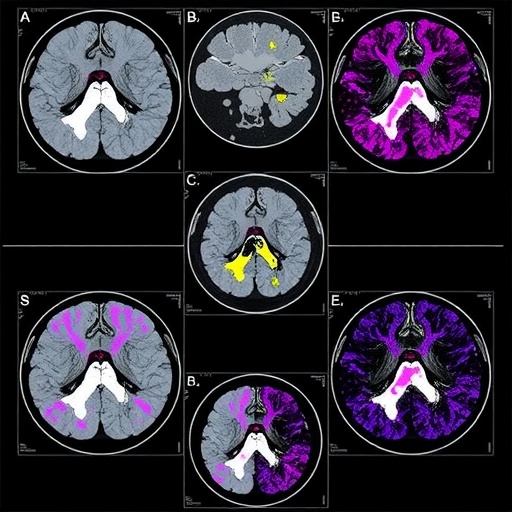

PRET’s core advancement lies in its departure from conventional AI methodologies. Whereas most existing models require tens of thousands of annotated pathology images and labor-intensive training routines, PRET introduces the concept of in-context learning—borrowed from natural language processing—to pathology image analysis. This approach allows the model to dynamically adapt to new diagnostic tasks on the fly by referencing only one to eight annotated tumor slides during inference, bypassing the need for explicit model fine-tuning or retraining sessions. This capability establishes PRET as a versatile, plug-and-play diagnostic tool capable of cancer screening, precise tumor subtyping, and meticulous tumor segmentation.

The research team’s collaboration with prestigious institutions including Guangdong Provincial People’s Hospital and Harvard Medical School ensured extensive validation of PRET’s clinical efficacy. The system was rigorously tested across 23 international benchmark datasets representing 18 distinct cancer types from facilities spanning the Chinese Mainland, the United States, and the Netherlands. This comprehensive evaluation demonstrated PRET’s superiority over existing diagnostic algorithms in 20 clinical tasks, with exceptional Area Under the Curve (AUC) performance metrics exceeding 97% in 15 separate challenges. PRET notably achieved a perfect AUC score of 100% in colorectal cancer screening and near-perfect 99.54% accuracy in esophageal squamous cell carcinoma tumor segmentation.

Arguably the most outstanding demonstration of PRET’s capabilities was observed in the detection of lymph node metastases—a highly complex and laborious diagnostic task. Utilizing merely eight slide samples, PRET attained an AUC of approximately 98.71%, distinctly surpassing the average performance of a panel of 11 pathologists whose AUC hovered around 81%. This dramatic performance leap underscores the system’s tremendous potential to alleviate human diagnostic burdens and enhance accuracy in areas traditionally plagued by variability and high error rates.